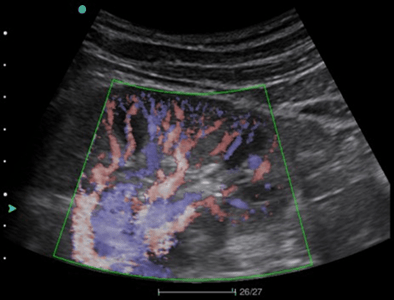

- VS Flow